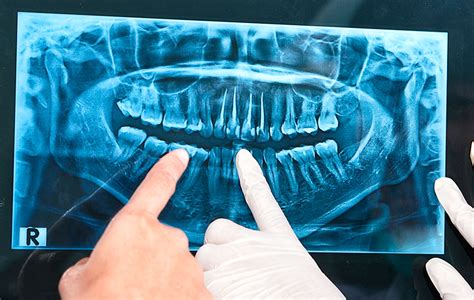

La ortopantomografía (radiografía de toda la boca) nos ayudará a determinar el nivel óseo general, presencia de terceros molares (muelas del juicio), lesiones en las raíces de los dientes (granulomas infecciosos), etc.